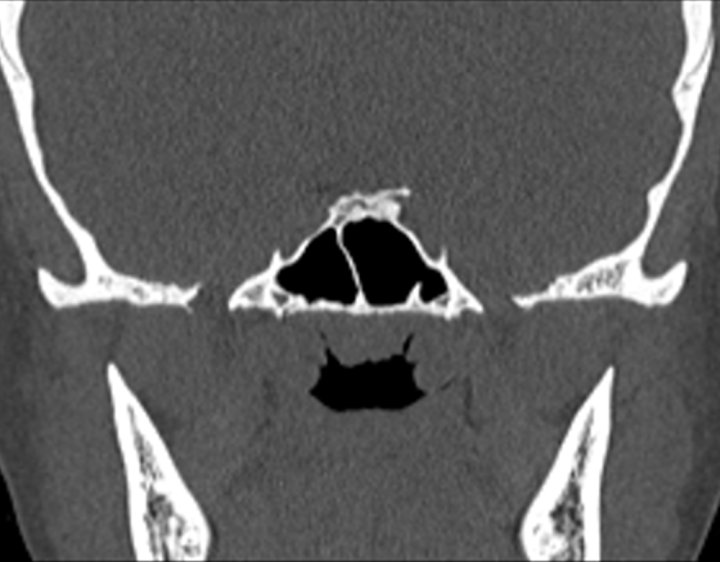

Click any image for labels.